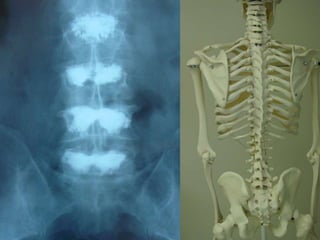

Sacroiliitis

 30 year old man with LBP HLAB27+

Synovitis, subchondral edema, iliac side more common